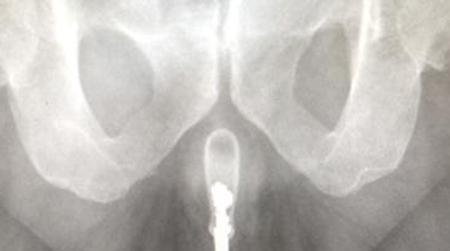

X-rays showed it there, and doctors used "copious lubrication" and forceps to remove it.